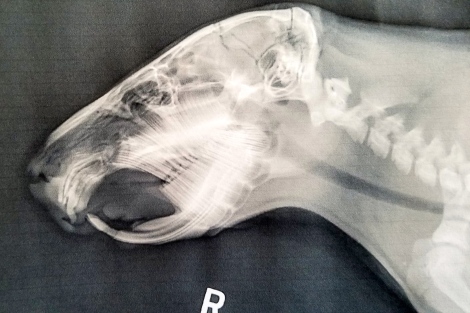

Contrast Dobby’s robust, although fractured, teeth with the oddly shaped teeth of Gidget:

Dobby’s upper incisors show up like a uniform, solid curve. The lower incisors line up with the uppers at the cutting surface.

Gidget’s upper incisors show as a conglomerate of wiggly lines above the palate. Her lower incisors have grown too far, there being no uppers to meet and sharpen them.

Rodents possess a “tooth bud” from which their teeth develop and grow. Similar to guinea pigs, capybaras are born with their eyes open, clad in fur, and equipped with teeth, ready to graze alongside the herd. Ideally, a tooth should emerge from the tooth bud with a smooth, uniform curve. The harder front enamel (the visible part of the tooth) and the softer back enamel (inside the mouth) allow the upper and lower incisors to sharpen each other into razor-like edges with each bite. While Gidget’s lower incisors are overgrown but mostly normal, her upper incisors are bizarrely misshapen, appearing like noodles. This unusual formation prevents her upper and lower teeth from functioning together like scissors to cut grass.